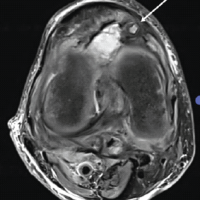

The patient remained asymptomatic till the 12-month follow-up, and a computed tomography was obtained, which revealed a fibrous non-union. However, the patient was asymptomatic and did not have any limp or abductor lurch, and the Harris Hip Score was 84. The head was viable, and options were explained to the patient, who opted for conservative management (Fig. 7).

Figure 7: X-ray at follow-up of 18 months.